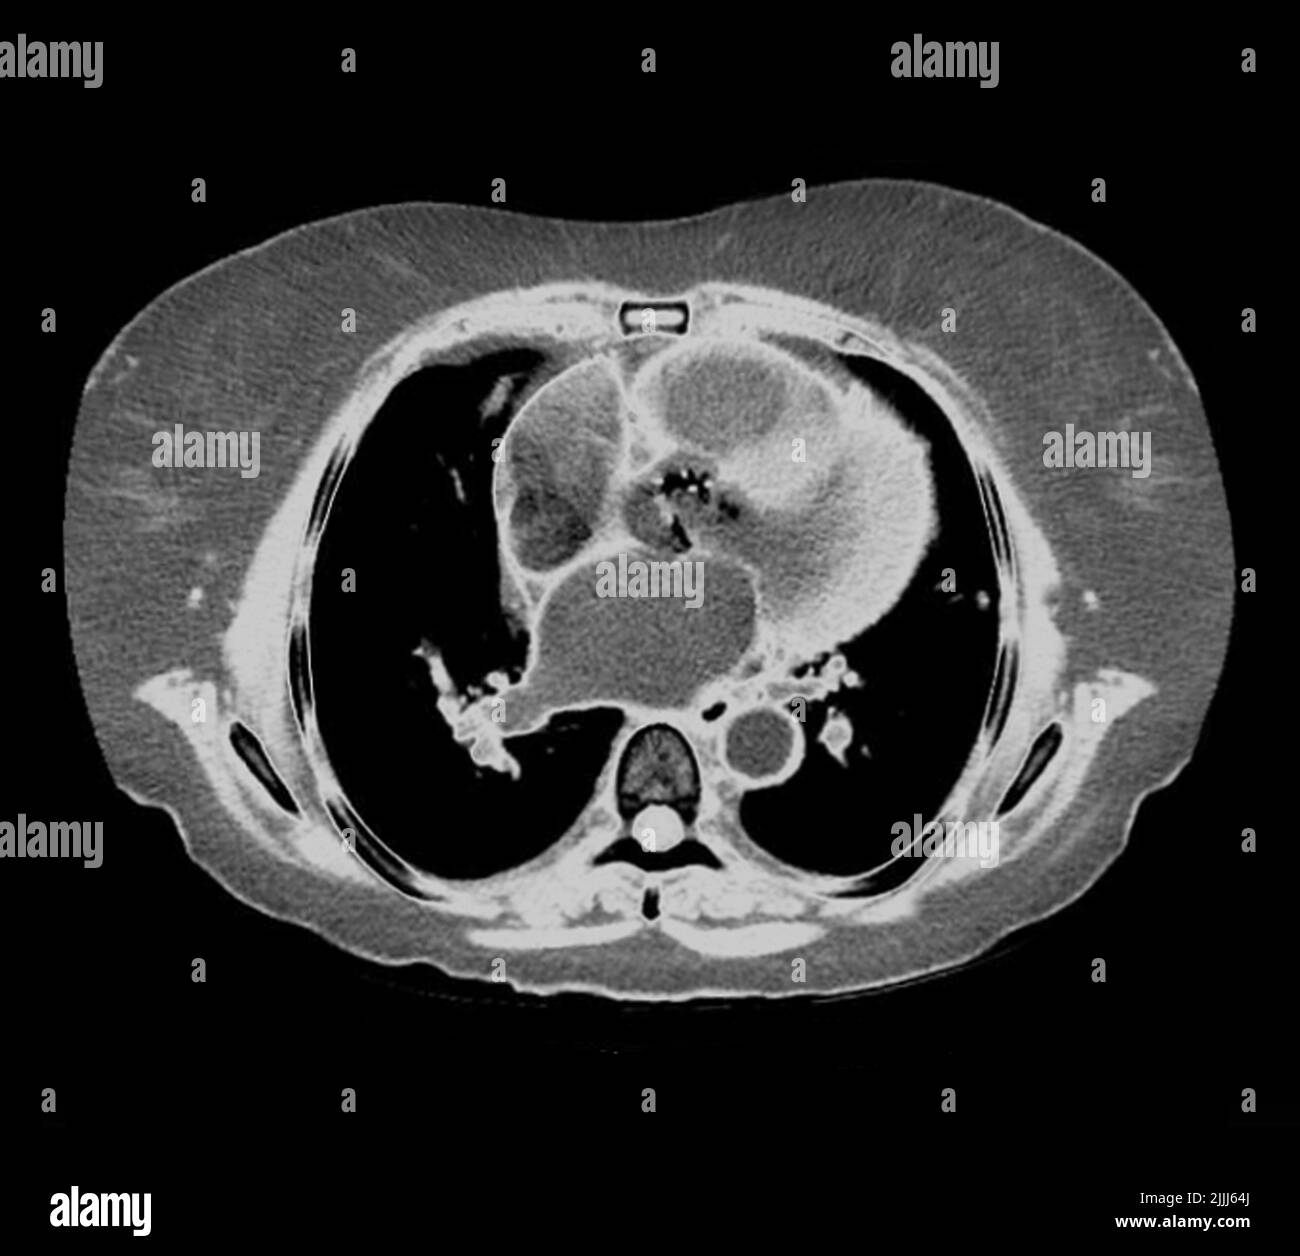

From pixels.com

Metastatic Pancreatic Cancer, Ct Scan Photograph by Du Cane Medical Can Endo Be Seen On Ct While it’s possible to see the effects of endometriosis on some scans (e.g. magnetic resonance imaging (mri’s), ct scans, and ultrasounds can help rule out certain conditions and, in some cases, confirm the likelihood that endometriosis is present. ct scans can detect endometrial lesions on the ureters, kidneys, and abdominal wall, but are not very. in most. Can Endo Be Seen On Ct.